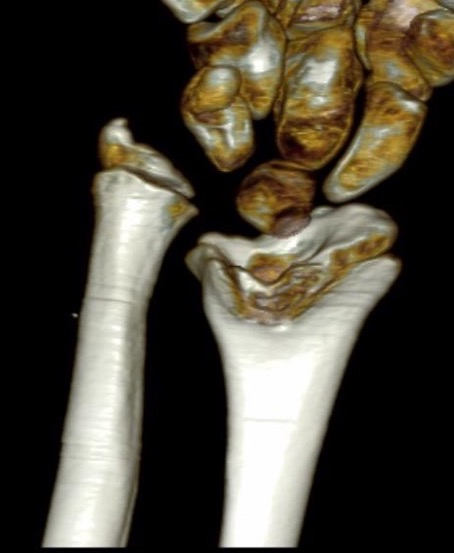

CT